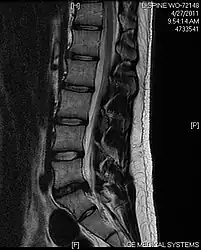

MRI scan of large herniation (on the right) of the disc between L4 and L5 vertebrae -

A rather severe herniation of the L4–L5 disc -

Example of a herniated disc at L5–S1 in the lumbar spine

- Magnetic resonance imaging is the gold standard study for confirming a suspected LDH. With a diagnostic accuracy of 97%, it is the most sensitive study to visualize a herniated disc due to its significant ability in soft tissue visualization. MRI also has higher inter-observer reliability than other imaging modalities. It suggests disc herniation when it shows an increased T2-weighted signal at the posterior 10% of the disc. Degenerative disc diseases have shown a correlation with Modic type 1 changes. When evaluating for postoperative lumbar radiculopathies, the recommendation is that the MRI is performed with contrast unless otherwise contraindicated. MRI is more effective than CT in distinguishing inflammatory, malignant, or inflammatory etiologies of LDH. It is indicated relatively early in the course of evaluation (<8 weeks) when the patient presents with relative indications like significant pain, neurological motor deficits, and cauda equina syndrome. Diffusion tensor imaging is a type of MRI sequence used for detecting microstructural changes in the nerve root. It may be beneficial in understanding the changes that occur after herniated lumbar disc compresses a nerve root, and might help in differentiating the patients that need surgical intervention. In patients with a high suspicion of radiculopathy due to lumbar disc herniation, yet the MRI is equivocal or negative, nerve conduction studies are indicated.[43] T2-weighted images allow for clear visualization of protruded disc material in the spinal canal.